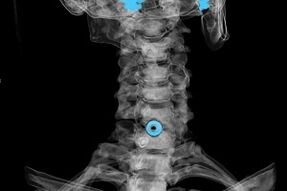

Diagnosis is established based on characteristic symptoms, as well as using:

- X-ray.This method is ineffective, especially in the last stages of the development of osteochondrosis.

- MRI (magnetic resonance imaging) of the cervical spine.A method that allows you to see the bone structure, the herniated intervertebral disc, its size and direction of development.

- Computed tomography.A less effective solution than MRI, because the presence and size of the hernia is difficult to determine.